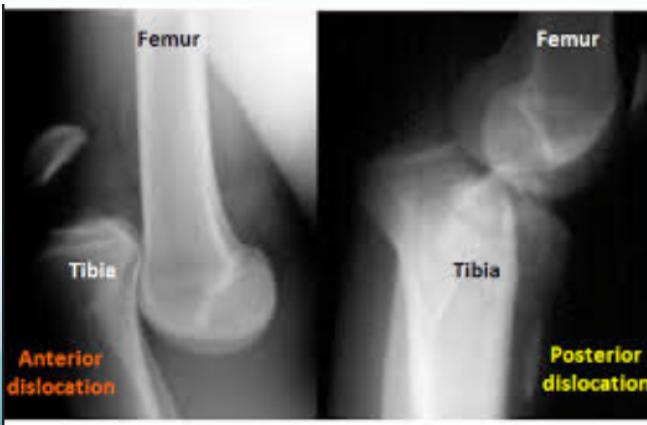

X-ray Findings:

- Dislocation

Vascular Assessment:

- Even if pulses are intact, perform angiography if there’s suspicion

- Angiography if distal pulses not felt

Management:

- Urgent reduction & vascular intervention if needed

- Then external fixation

- Reconstruction of ligaments (acute or delayed) Surgery